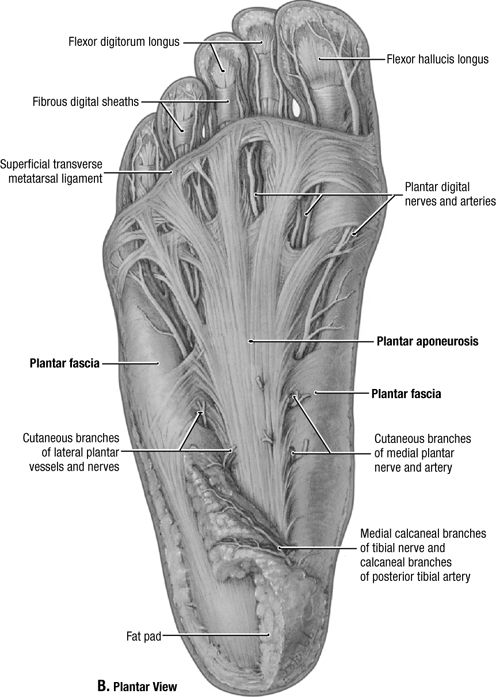

Wrist

Nontrauma, Infection

For typical wrist pain evaluations including arthritis or

mass. Good for carpal alignment. US: good for soft tissue masses,

tendon pathology. CT scan may be a useful adjunct to assess for occult

scaphoid fractures and for healing, as well as other occult injuries

such as hook of hamate fracture. CT is often used in the preoperative

workup of intraarticular distal radial fractures. MRI is good for occult

fractures, Kienböck’s, AVN of lunate or scaphoid, triangular

fibrocartilage tears, or intercarpal ligament injuries.

![]() |

|

Figure 5 (A) PA wrist. (B) Ulnar oblique wrist. (C) Lateral wrist.